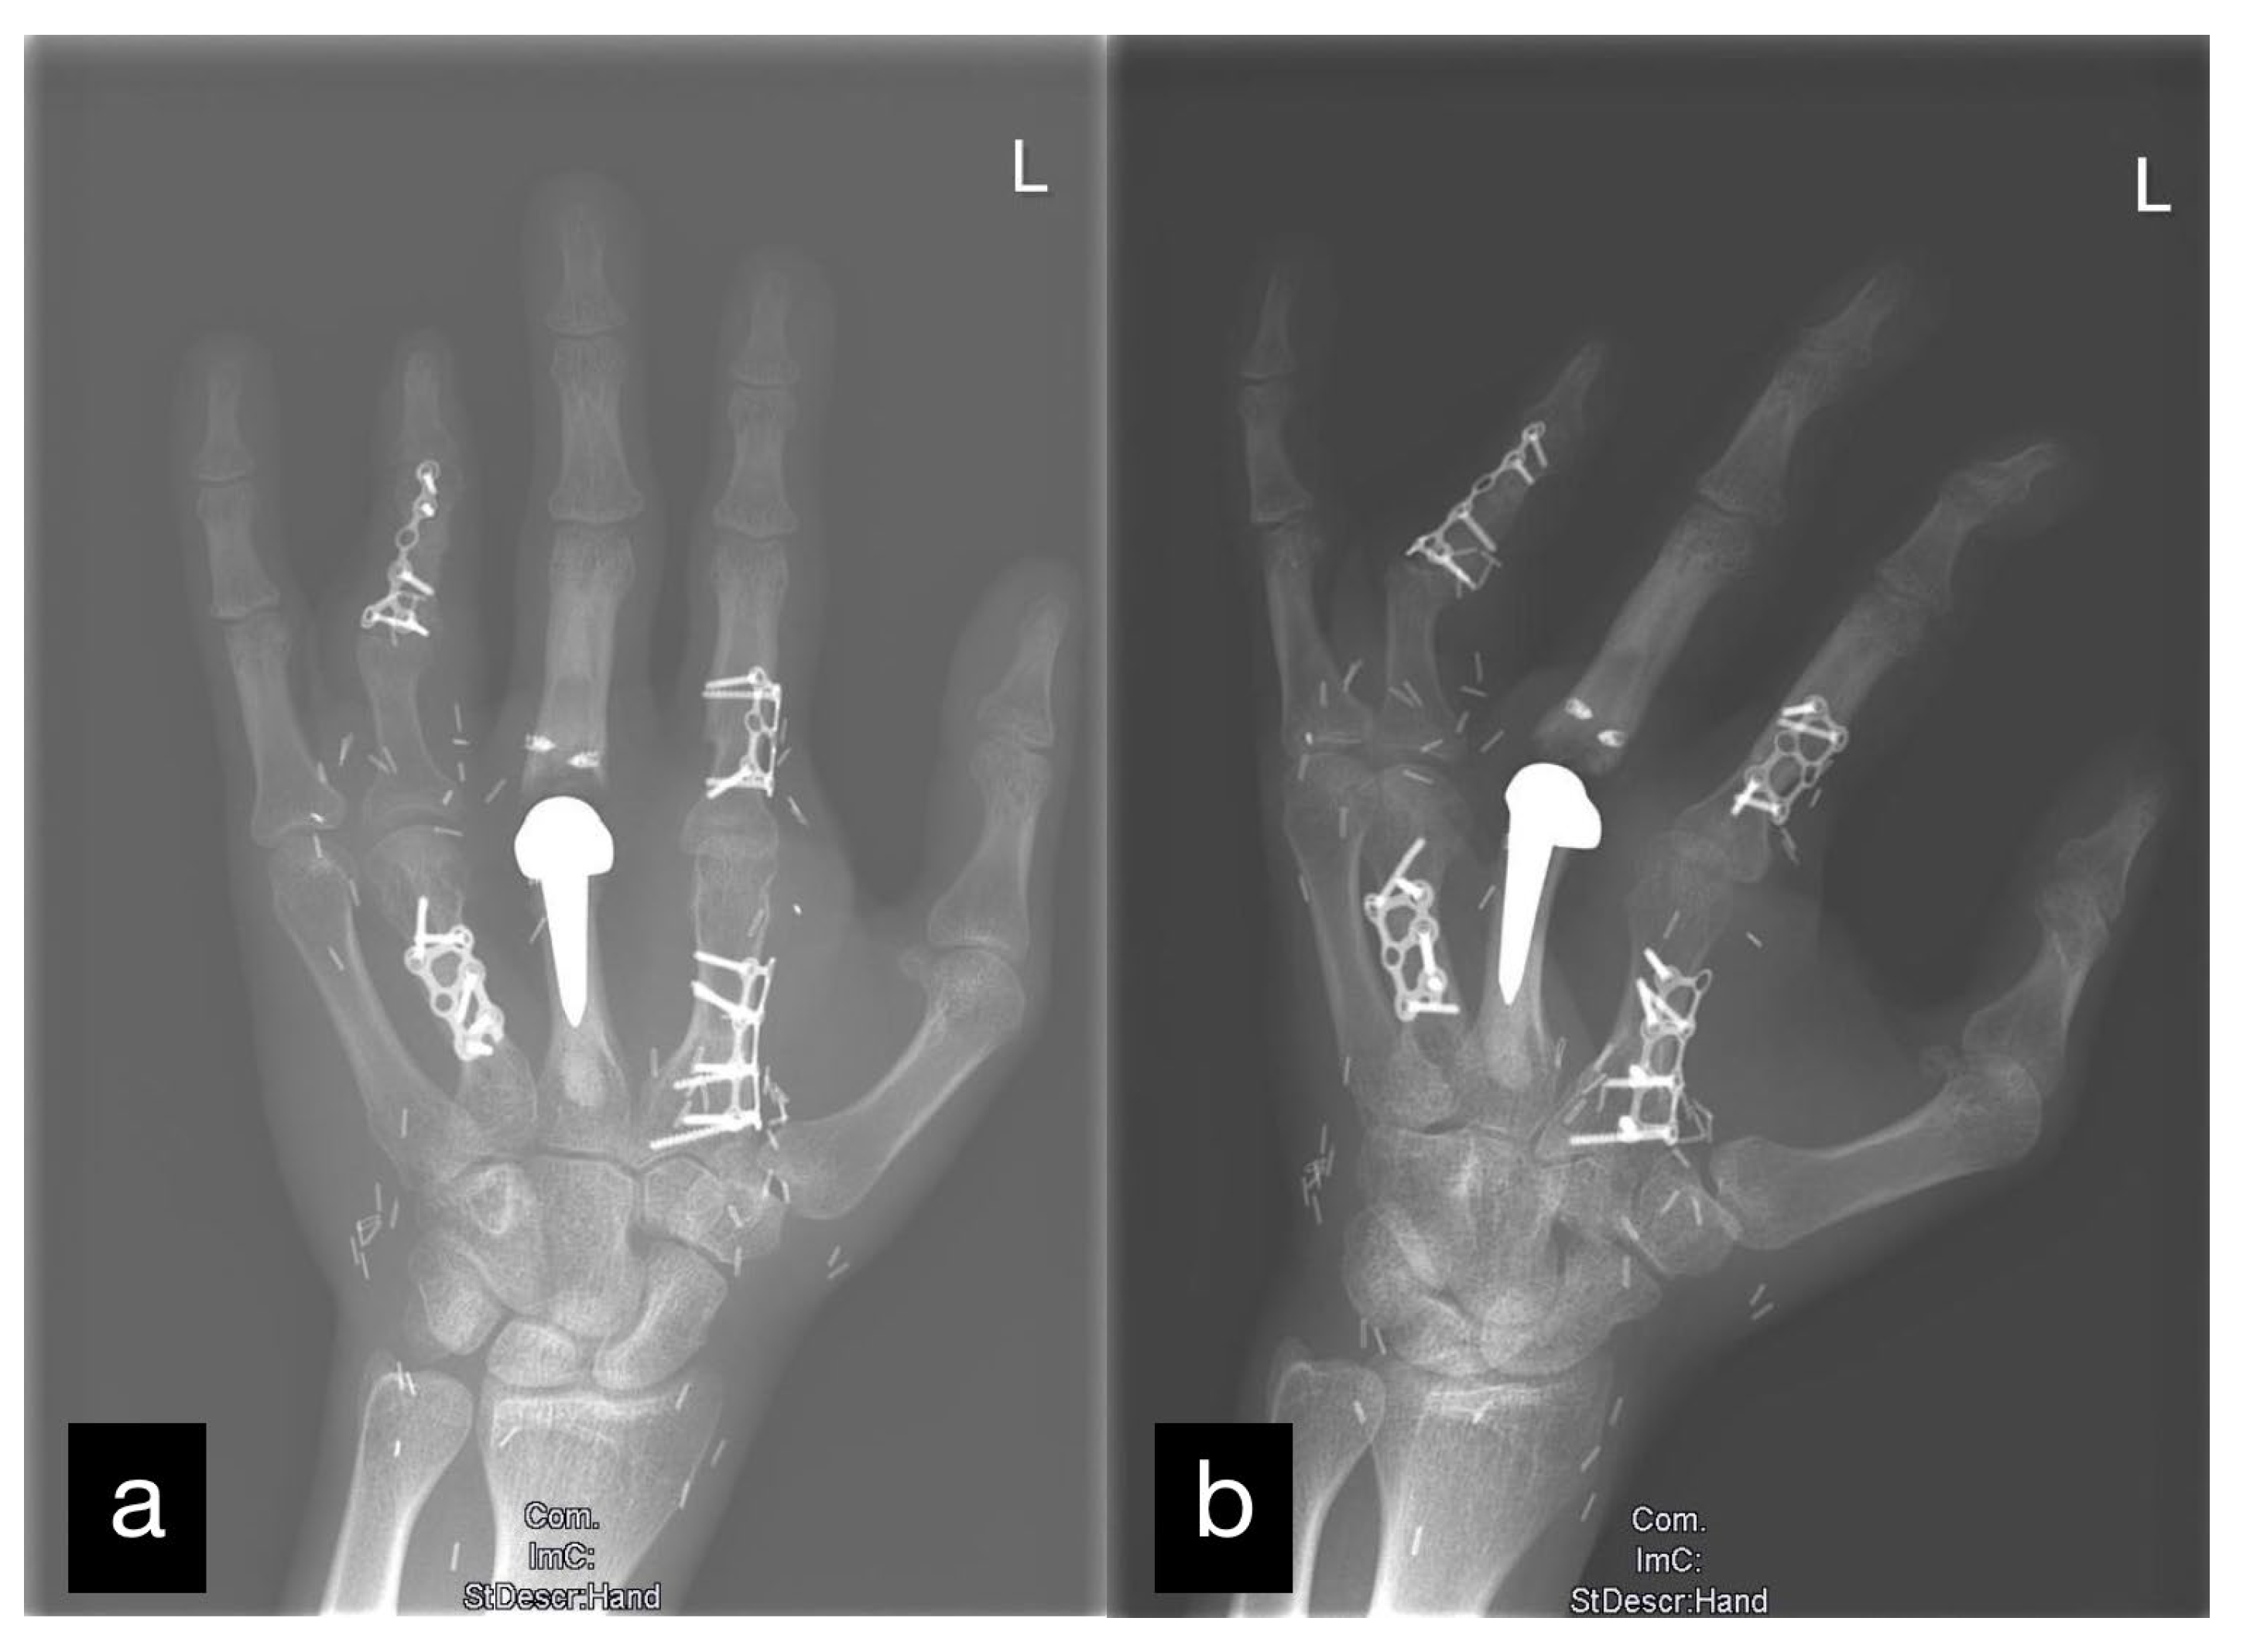

| 1 | 17 | m | Circular saw injury to the dominant left hand with a subtotal amputation of DII–DIV at the level of the MCP joints | Replantation of DIV Amputation of the distal metacarpals DII and DIII, PIP-Joint transfer to DII from the left second toe, MCP endoprosthesis DIII, Free double toe joint transfer to PIP and DIP from the right second toe | Finger-palm distance (FPD) DII–DV 0–0–1–0 cm Fingernail table distance (FNTD) DII–DV 0–0–0–0 cm Kapanji 10/10. DII: MCP 0–0–80°, PIP 0–0–100°, DIP 0–0–80°; DIII: MCP 0–0–80°, PIP 0–0–100°, DIP 0–0–50°; DIV: MCP 0–10–90°, PIP 0–0–90°, DIP 0–0–10°; DV: MCP 0–0–90°, PIP 0–0–100°, DIP 0–0–90°. | The two-point discrimination reached 4–6 mm in all fingers. | Pinch left 7 kg, right 10 kg. Force left 8 kg, right 18 kg. |